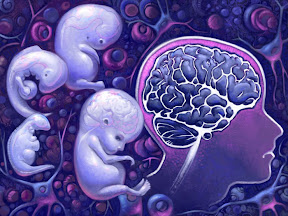

मेंदूच्या वाढीतील वेगवेगळे टप्पे (2)

मेंदूच्या वाढीतील वेगवेगळे टप्पे (2)

बाल्यावस्थेतील मेंदू

आईच्या पोटातून बाहेर पडलेल्या क्षणापासूनच बाळाचा मेंदू तल्लख व लवचिक राहतो. या थोड्याशा अवधीतसुद्धा चेतापेशींच्या लाखो जोडण्या होत असतात व लाखो जोडण्या तुटत असतात. अवती-भोवतीच्या निरीक्षणामधूनच बाळाच्या मेंदूची वाढ होऊ लागते. कदाचित शिकणे, आठवणीत ठेवणे व भाषाज्ञान या गोष्टी बाळ जन्म घेण्याअगोदरसुद्धा घडत असावेत. प्रसवपूर्व काळात मेंदूमध्ये दर मिनिटाला अडीच लाख या प्रमाणात पेशी नव्याने तयार होत राहतात. व दर सेकंदाला 18 लाख जोडण्या जोडल्या जात असतात. यातील सुमारे पन्नास टक्के पेशी नाहिशा होत असल्या तरी उरलेल्या पेशींचा वापर मेंदूच्या रचनेसाठी होत असतो. बाळ जन्मल्यानंतरचा पुढील दहा वर्षाचा काळ मेंदूच्या वाढीसाठी व त्याच्या विकासासाठी महत्वाचा ठरतो. याच कालखंडात प्रत्येक छोटे मोठे अनुभव गाठीशी बांधले जात असतात. ही अनुभवाची शिदोरीच माणसाला घडवत असते. म्हणूनच या बाल्यावस्थेतच मेंदूचा जास्तीत जास्त विकास करण्याची व तिला प्रभावशाली बनवण्याची जवाबदारी पूर्णतया पालकावरच असते.

प्रसवपूर्व काळातील अनुभव मेंदूच्या विकासासाठी अत्यंत महत्वाचे आहेत. गर्भधारणेनंतरच्या 22-24 आठवड्यावंतर भ्रूणाचा मेंदू बाहेरच्या आवाजाला किंवा स्पर्शाला प्रतिसाद देऊ शकतो. परंतु तीच गोष्ट पुन्हा पुन्हा घडत असल्यास त्यात नाविन्य नसल्यामुळे मेदू दुर्लक्ष करू लागतो. 32 व्या आठवड्यानंतर अर्भकाचा मेंदू गुंतागुंतीच्या, क्लिष्ट व/वा पुन्हा पुन्हा घडत असलेल्या आठवणी साठवू लागतो. काही गाण्यांच्या लयी, आईचा आवाज अशा गोष्टी गर्भधारणेच्या तिसाव्या आठवड्यापासून बाळ जन्माला येईपर्यंत मेंदूत साठवल्या जाऊ शकतात.

गर्भावस्थेतील भ्रूणाचा मेंदू व बाळाच्या जन्मानंतरचा मेंदू यात तसा फार मोठा फरक जाणवत नाही. मूल जन्माला यायच्या आधीपासूनच मेंदूच्या बाह्यक (cortex) मध्ये स्पर्श संवेदना जाणवते. जन्मानंतरच्या पुढील 2-3 महिन्यात मेंदूचा बाह्यक स्वयंचलन, कार्य-कारण व दृष्टिकोन इत्यादींचे नियंत्रण करू लागतो. पुढील 6 महिन्यात अग्रमस्तिष्क (frontal lobe) भावनांचा विकास, त्यांचे उत्तेजन, व्यावहारिक स्मृती व एकाग्रता यासंबंधीची कामं करू लागते. आपण कुणीतरी आहोत ही जाणीव विकसित होण्यासाठी मेंदूतील पार्श्व व अग्र मस्तिष्क (perinatal & frontal) यामधील मंडल (circuitry) पूर्ण व्हावी लागते. त्यासाठी सुमारे 18 महिन्याचा काळ लागतो. आपल्याप्रमाणे इतरांनासुद्धा जाणीव असू शकते याचे भान येण्यासाठी वयाची 3-4 वर्षे जावे लागतात.